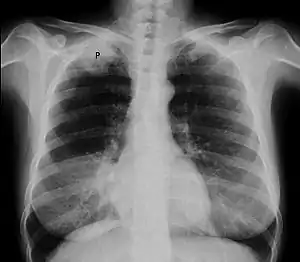

| Chest X-ray showing a Pancoast tumor (labeled as P, non-small cell lung carcinoma, right lung), from a 47-year-old female smoker. | |

Diagnosis of Pancoast tumor is usually made after evaluating clinical symptoms and imaging. Chest X-ray is a good screening test even though a CT scan of the chest can provide a better resolution and extent to which internal organs are being compressed.